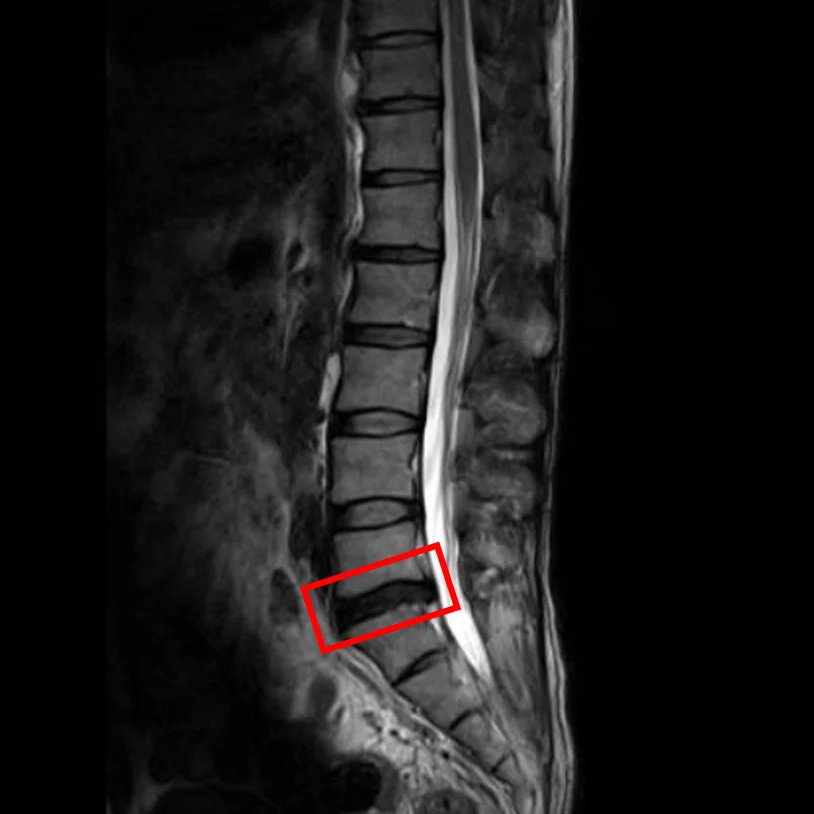

По данным МРТ и результатам осмотра пациента выявлена межпозвоночная грыжа диска L5/S1.

Симптомы по 10-балльной шкале (0 – отсутствие симптомов, 10 – сильные боли/онемение):

– боли в пояснице: 6;

– боли в ногах: 0;

– онемение в ногах: 0;

– боли в ягодицах: 0.